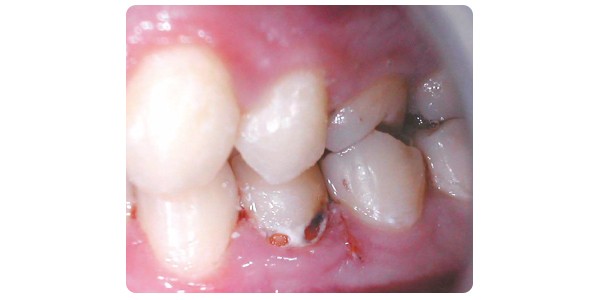

Le concept d’intervention minimale (IM) en dentisterie englobe l’ensemble des mesures préventives et interceptives à mettre en œuvre pour enrayer l’apparition et la progression des maladies affectant les tissus durs dentaires et le parodonte. Il est applicable à tous les domaines de la dentisterie, en particulier à la cariologie. L’IM s’intéresse aux causes et non uniquement aux symptômes de la maladie [1, 3, 4]. En cariologie, son champ est large : il comprend la détection des lésions le plus précocement possible, la mise en évidence et la gestion des facteurs de risque (évaluation du risque carieux ou ERC) ainsi que la mise en œuvre de stratégies préventives et interceptives ciblées, l’éducation du patient et son suivi. Lorsque les symptômes de la maladie sont présents (lésions carieuses), d’autres stratégies interceptives s’imposent, mais les solutions les moins invasives seront alors privilégiées : reminéralisation, scellement thérapeutique, infiltration résineuse et soins restaurateurs épargnant le plus possible les tissus résiduels sains [5].